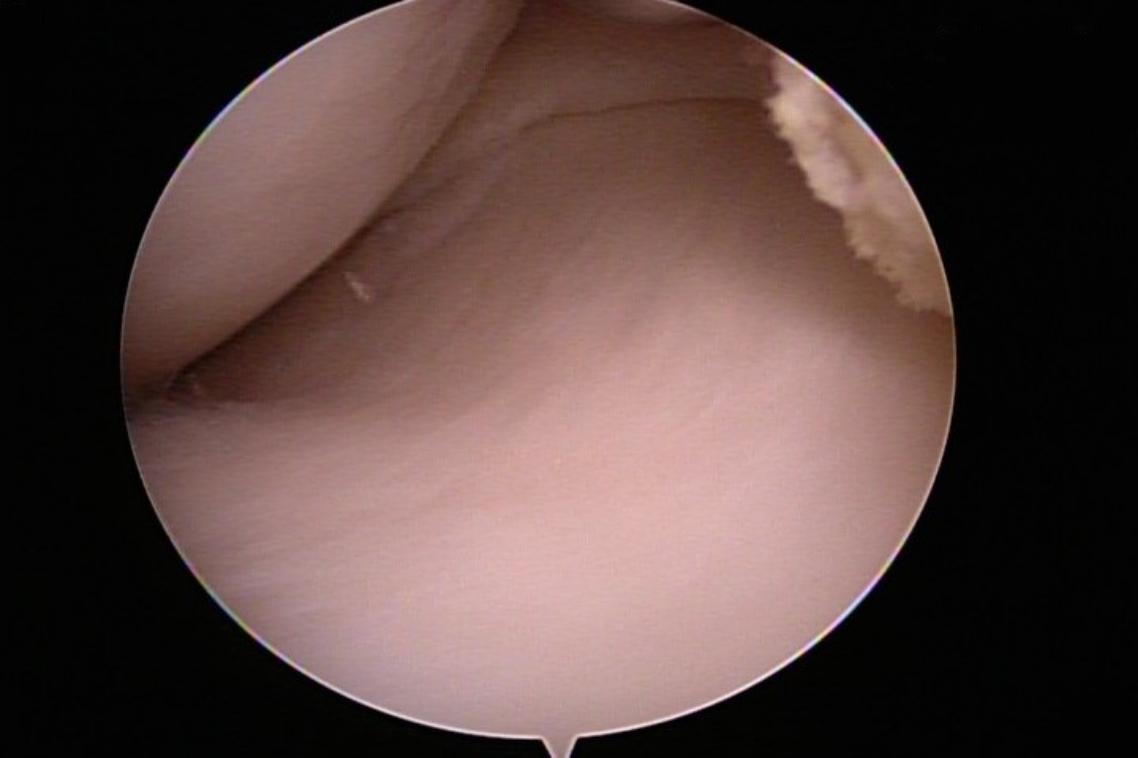

清除乾淨的膝關節腔(圖片來源/林心畬醫師提供)

傳統手術需要切開整個關節來移除碎片或修補軟骨,傷口大,復原慢,有時還會遇到手術後沾黏僵硬的後遺症。但是現在內視鏡技術已經普及化,搭配關節專用的內視鏡器械,只需要3個小於1公分的傷口便可完成手術,手術後隔天傷口只會些微腫脹,通常一天內可以恢復獨立下床與走路,住院時間只需2天1夜。

除了修補軟骨及移除碎片,手術中還可以詳細檢查關節內的狀況,若是發現不平整的皺壁或是發炎的滑膜組織也可同時清除,回復關節的順暢度,延長關節的使用年限。